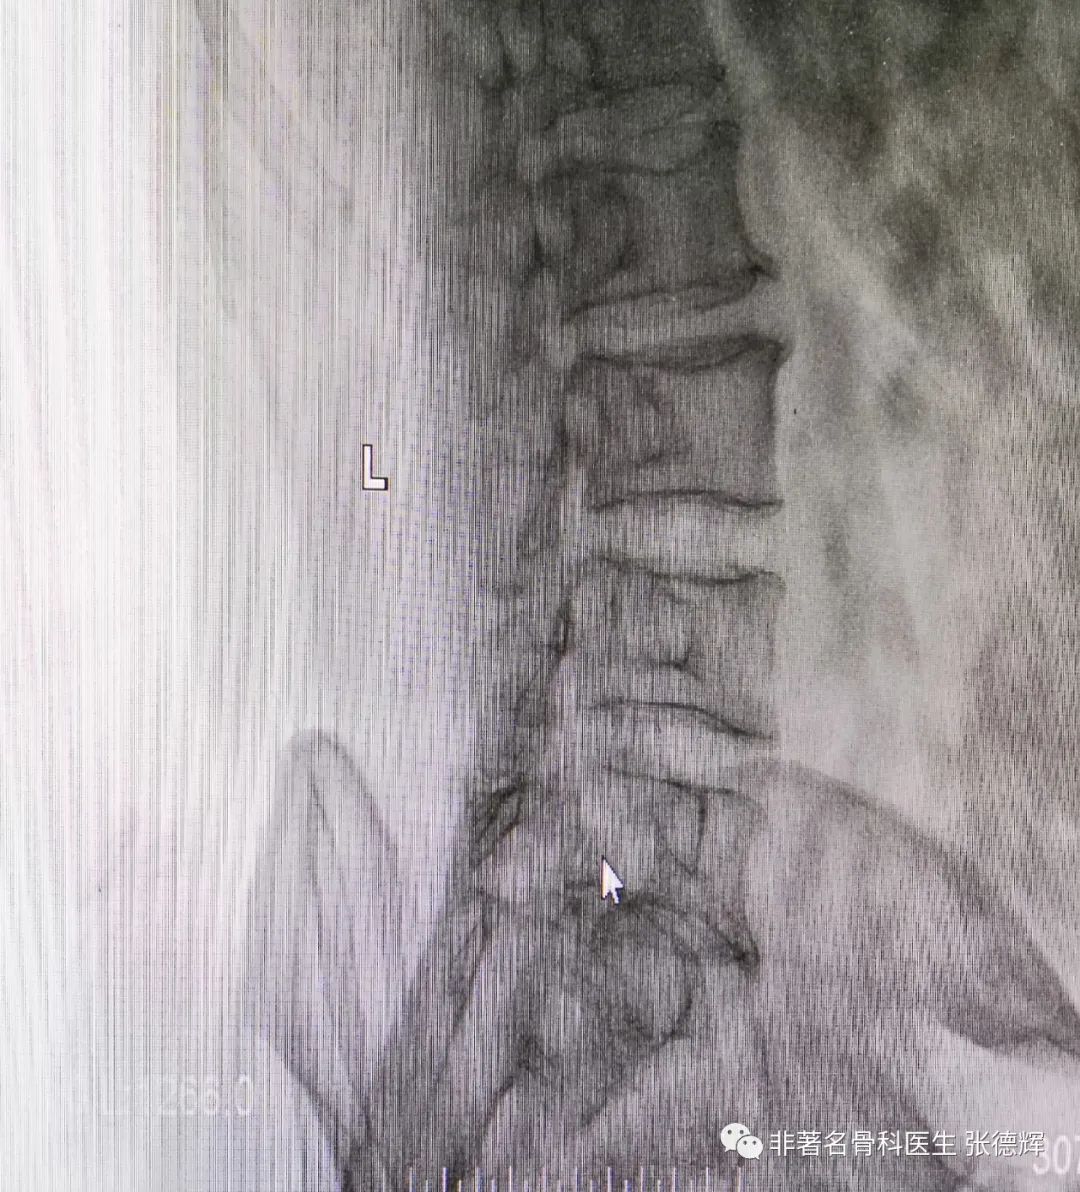

近期接诊一位腰椎峡部裂的患者,体重接近100公斤,腰腿痛近1年,严重时行走障碍,以下是影像检查资料。可以看到是明显的 腰5双侧峡部裂并轻度滑脱 。

腰椎双侧斜位片可见腰5双侧峡部骨质不连续

(“狗颈征”阳性,鼠标指示处)